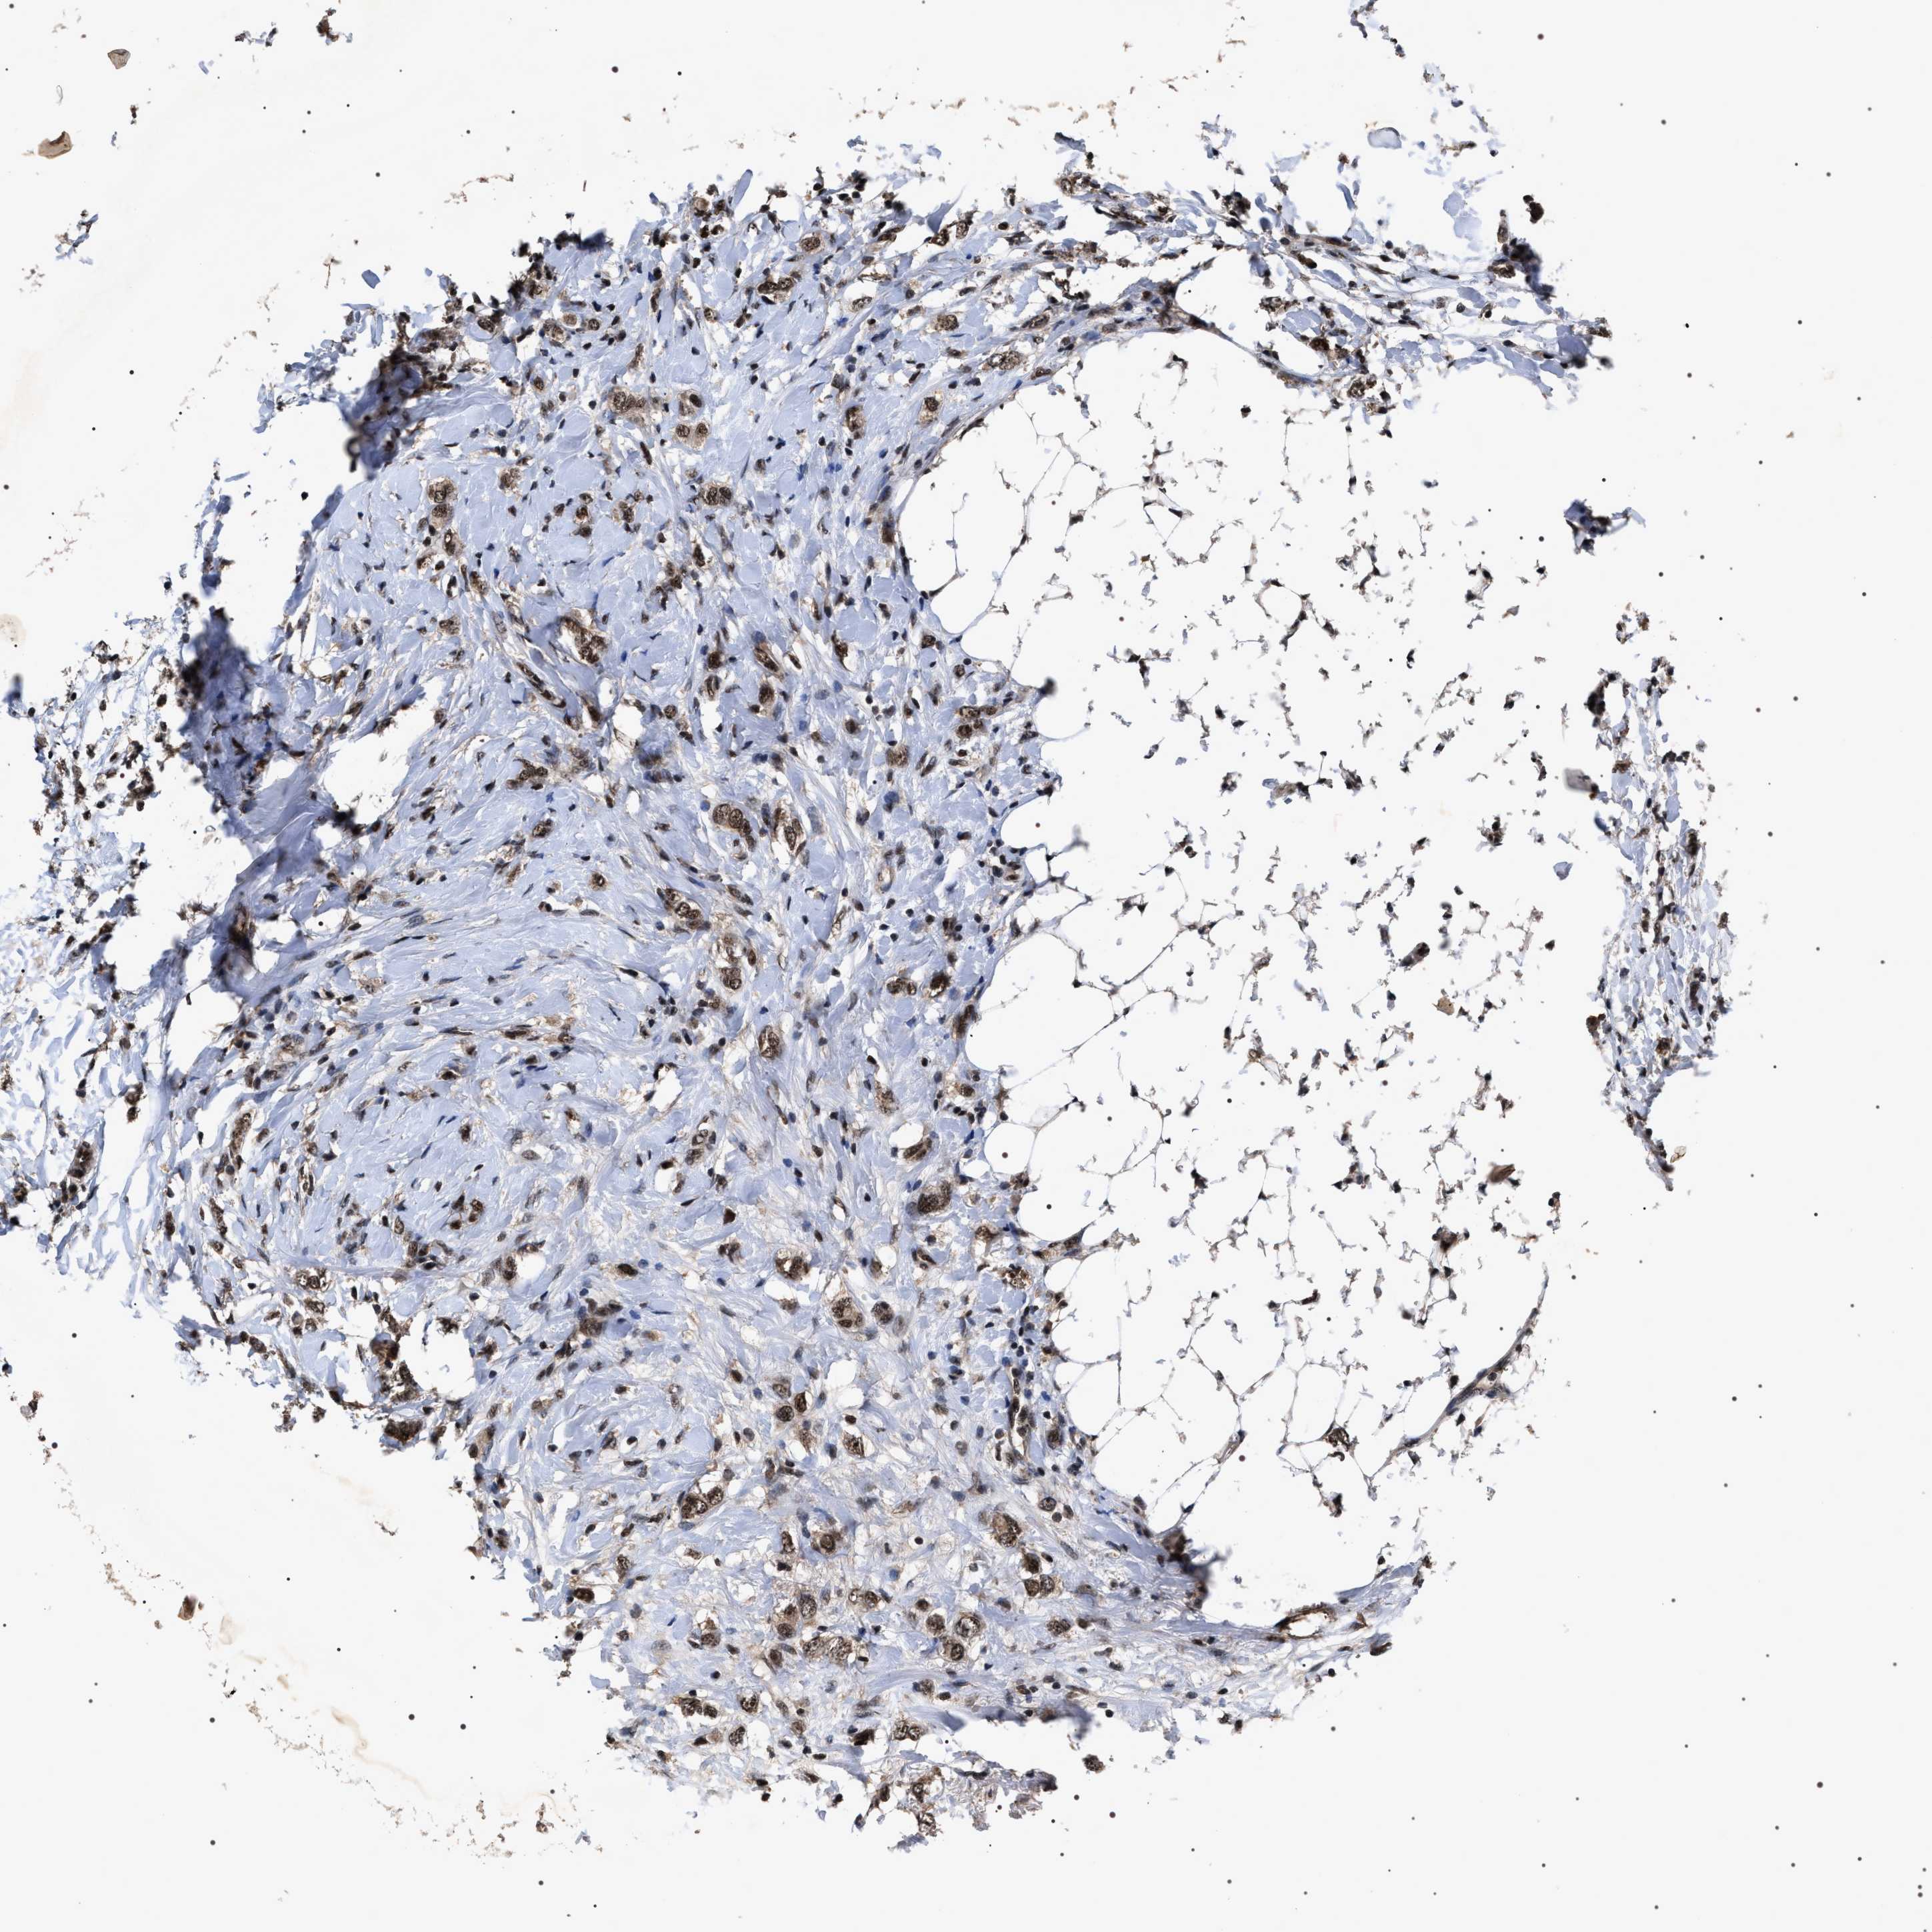

Breast cancer

Human cancer